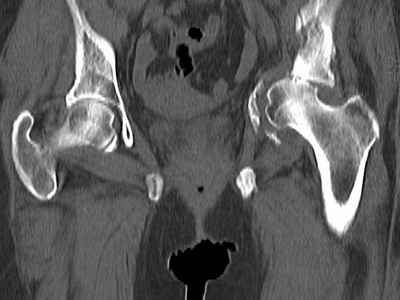

Уважаемые коллеги, возник вопрос по лечению нашей пациентки 60 лет. Около года назад множественная травма: в том числе Т-образный перелом вертлужной впадины.

На сегодняшний день сращение отломков имеется на ограниченных участках, имеется дефект задней колонны вертлужной впадины. Движения неплохие, ходит с костылями, приступая на ногу.

По мнению эдопротезистов при установке антипротрузионного кольца или октопуса не хватит костного материала и необходимо перед протезированием выполнить реконструкцию впадины, иначе чашка протеза неминуемо выпадет.